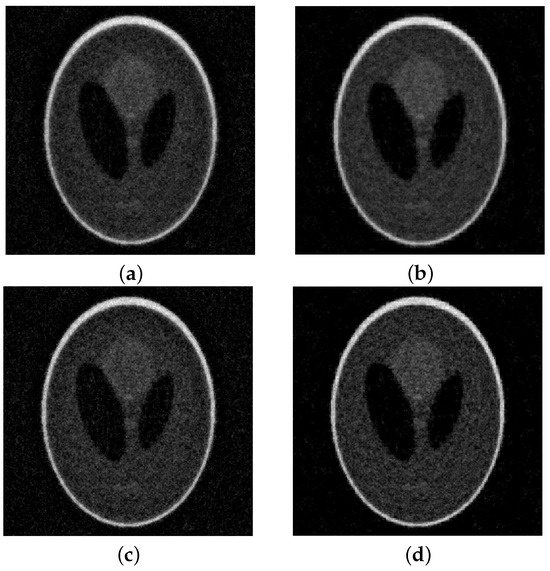

As mentioned above, we compare our algorithm with lsqr and SIRT. As stated above, we expect the solution to be nonnegative and, therefore, in our method, we project the computed solution into the nonnegative cone at each iteration. To improve its accuracy further, we perform the same projection in the lsqr method ensuring that all the computed solutions are physically meaningful. In all the tests, the SIRT method performed worse than the others, computing not very accurate reconstructions and requiring a large amount of iterations to converge. In Figure 3, we report the evolution of the RRE against the iterations for all considered methods and noise levels. We can observe that semi-convergence is more evident for the lsqr method than for our algorithmic proposal. Regardless of the considered, our method is more stable than lsqr as the RRE increases much slower. We can also observe that the convergence is the most stable when . This is more evident for higher levels of noise. It is clear that, for the lsqr method, if one overestimates the stopping iteration, then the RRE may become extremely large. This is not the case for our MGM methods. In Table 1, we report the RRE obtained at the “optimal” iterations, i.e., the one that minimizes the RRE, and at the DP iteration. In all cases, we can observe that our method is more accurate than the lsqr algorithm, albeit at a generally higher computational cost. However, we would like to stress that the cost per iteration of both lsqr and the MGM is of the same order of magnitude as one matrix-vector product with A and one with , as analyzed in [16]. Since A is extremely sparse, this cost is ; therefore, performing few iterations is computationally extremely cheap. For the noise level, , we report the solutions computed by lsqr and by the MGM with in Figure 4.

Figure 4.

Shepp–Logan (full angles) with 10% noise. On top of the reconstructions obtained at the DP iteration: (a) lsqr, (b) MGM, . At the bottom, the optimal reconstructions: (c) lsqr, (d) MGM, .